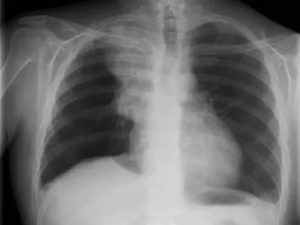

Стандартный рентген лёгких делают в двух проекциях. На них отчётливо просматриваются лёгочная ткань, кости (рёбра, ключицы, плечевой пояс), купола диафрагмы, накладывающиеся друг на друга тени сердца, сосудистого пучка, органов средостения, позвоночника, грудины.

Лёгкие – это орган, наполненный воздухом. Рентгеновские лучи через него проходят практически беспрепятственно. Поэтому лёгочное поле будет выглядеть, как просветлённый участок, окрашенный на рентгенограмме в чёрный цвет. Твёрдые ткани (кости), наоборот, визуализируются белыми. Корни лёгкого, будучи более плотными, чем лёгочные поля, задерживают часть лучей, поэтому они немного светлее.

На рентгенографическом снимке, выполненном в передней проекции, контуры легких образуют легочные поля, по всей площади, пересекаемые симметричными тенями ребер.

Крупная тень, между легочными полями образуется совокупным наложением проекции сердца и магистральных артерий.

В пределах контура легочных полей, можно увидеть корни легких, расположенные на одном уровне с передними концами 2 и 4 ребер и незначительное затемнение площади, вызываемое богатой сосудистой сетью, располагающейся в ткани легких.